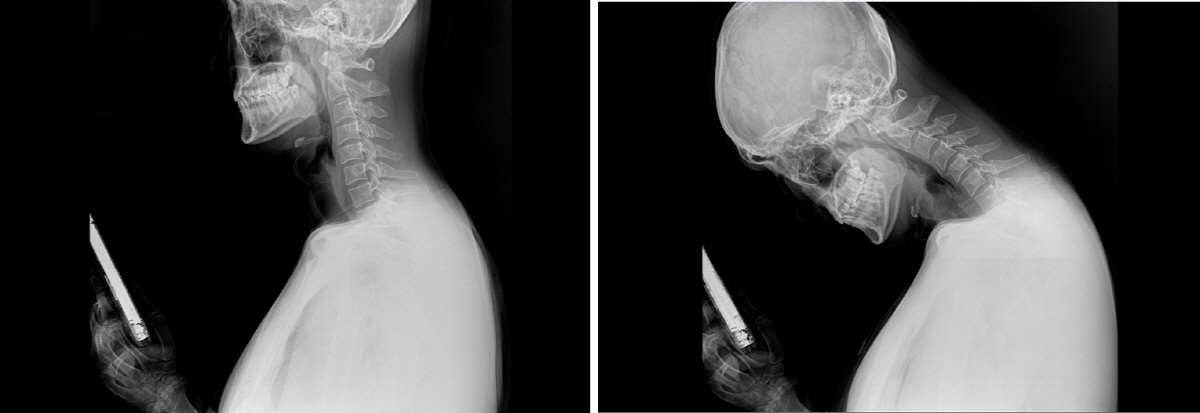

연령별로 살펴보면 유아동의 과의존 위험군이 가장 큰 폭으로 증가했고, 성인과 60대 이상 노년층의 과의존 위험군도 매년 증가 추세를 유지하고 있다. 스마트폰의 보급은 생활의 편리함과 즐거움은 커졌지만 의존도가 높아짐에 따라 척추, 관절 통증 등 건강에 경고등이 켜졌다. 특히 스마트폰을 보기 위해 고개를 내밀고 있거나 장시간 고개를 아래로 떨구고 있는 등의 잘못된 자세는 목디스크(경추 추간판탈출증)를 유발하게 된다. 고개를 숙이면 머리가 떨어지지 않도록 붙잡는 목 근육의 수축력이 함께 작용하면서 목에 가해지는 무게는 머리 무게의 5배에 이른다. 머리 무게가 7㎏이라면 목에 가해지는 무게는 무려 35㎏이 되는 셈이다.

목 디스크는 중년 이후 퇴행성 변화에 의해 추간판에 수분이 줄어 탄력이 떨어지면서 발생하는 경우가 많아 주로 40~50대 발생하는 질환이다. 7개의 경추(목뼈)로 이루어진 목은 목뼈에 가해지는 압력과 충격을 분배하기 위해 C자 형태를 이루고 있다. 이러한 형태의 목은 하중을 받았을 때 스프링처럼 쿠션역할을 한다. 그런데 목을 길게 빼며 고개를 떨구고 스마트폰을 보는 자세는 목의 커브가 없어지면서 정상적인 움직임의 균형을 깨뜨리고 목과 어깨에 통증을 유발한다. 또한 이런 자세는 목 주변 근육과 인대를 긴장시키고 일자목을 만들기도 하는데, 이를 치료하지 않고 방치할 경우 목뼈 사이에 있는 수핵이 밀려나와 신경을 압박하는 목디스크로 이어질 수 있다.